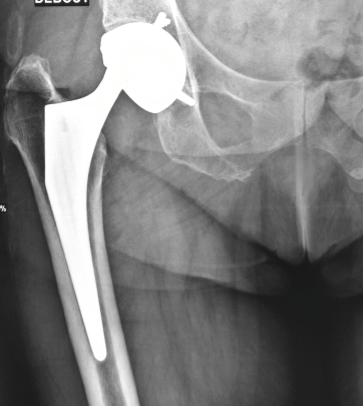

Examples of revision for periprosthetic fracture (PPF)

Case report n°1 (Figure 1)

- PPF at the cementless pivot (Vancouver B2)

- Two component revision: cementless monoblock long stem non-locking, fracture repair with cerclage wiring

- Dual mobility cup